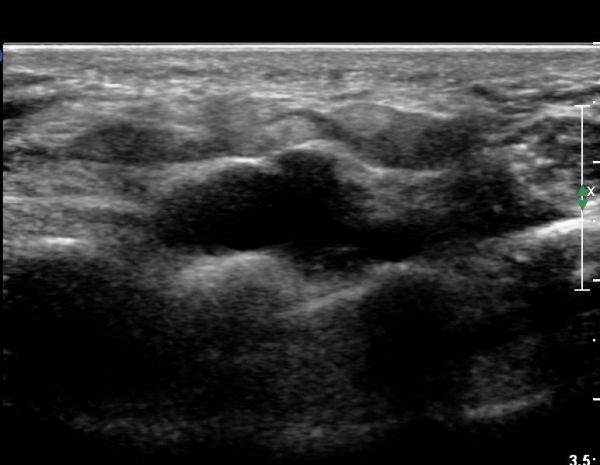

4 sono.jpg

¼Õ¹Ù´Ú ºÎÀ§¿¡¼­ ô°ñ½Å°æ ½ÉºÎ °¡Áö º´Áõ

(periphral neuropathy  of  deep palmar branch of ulnar nerve at palm level).